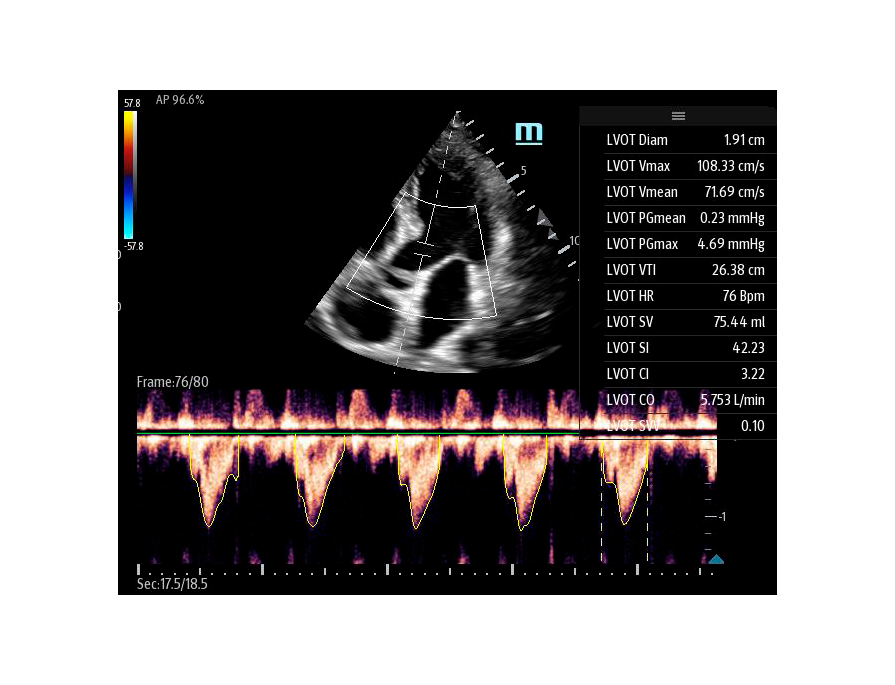

Автоматическая оценка потока выносящего тракта – Smart VTI

Чтобы использовать уравнение, нужно получить поток выносящего тракта левого желудочка в PW допплере — это достаточно кропотливая работа. В ультразвуковых системах Mindray Resona i9 эта задача решается автоматической оценкой потока выносящего тракта – Smart VTI.

Доктору остается получить 5-ти камерное сечение сердца и нажать одну кнопку на сенсорном экране. Прибор сам выберет расположение контрольного объема, получит спектрограмму и обведет спектр с расчётом всех показателей. Быстро и эффективно.